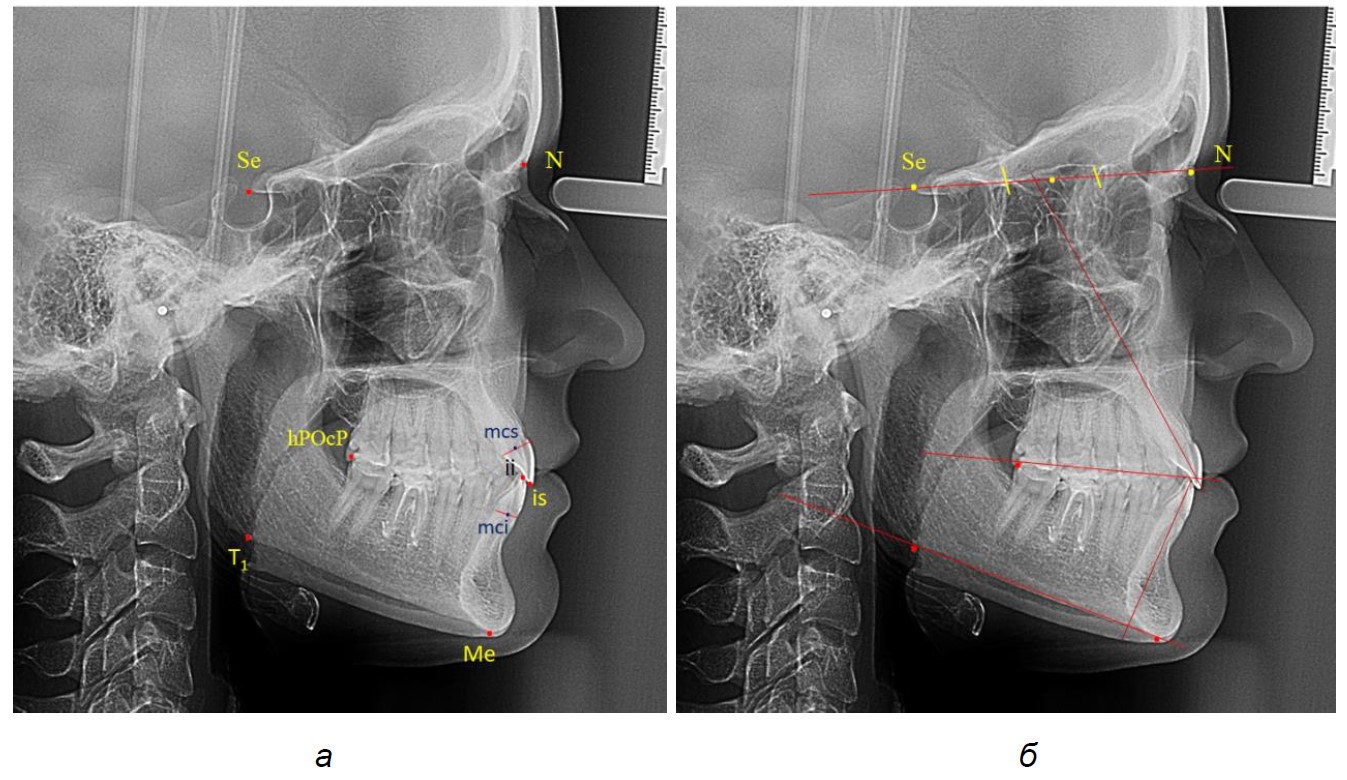

Указанные точки соединяли линиями, которые служили для измерения угловых параметров (рис. 1).

Рис. 1. Расположение точек (а) и линий (б) для исследования резцов на боковой телерентгенограмме

Межрезцовый угол измеряли между условными срединными вертикалями резцов верхней и нижней челюсти. Окклюзионная линия разделяла межрезцовый угол наверхнюю и нижнюю части. Измеряли угол наклона верхнего резца к линии N-Se и угол наклона нижнего резца к мандибулярной линии. С учетом того, что межрезцовый угол весьма вариабелен, среднестатистические показатели верхнерезцового и нижнечелюстного угла были распределены по 3 типам, в частности, мезотрузионный, протрузионный и ретрузионный. Таким образом, были выделены 9 групп, для которых были рассчитаны угловые показатели.